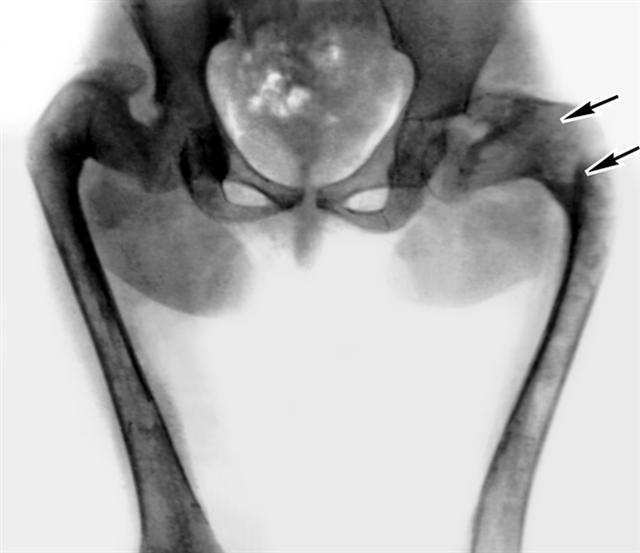

Рис. 1б). Девочка с полиоссальной формой фиброзной остеодисплазии: на рентгенограмме таза и бедренных костей отмечаются деформации бедренных костей по типу «пастушьей палки», структура пораженных костей напоминает матовое стекло с участками разрежения (указаны стрелками), кортикальный слой не истончен.